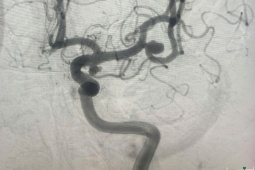

Các bác sĩ phẫu thuật bắc cầu động mạch não cho người bệnh. (Ảnh: BVCC)

Tại khoa Ngoại thần kinh, Bệnh viện Chợ Rẫy, kết quả chụp MRI tưới máu não và DSA động mạch não ghi nhận dấu hiệu của Moyamoya – bệnh lý tắc nghẽn mạch máu não bẩm sinh hiếm gặp. Đây là dạng bệnh mạch máu não tiến triển đặc trưng bởi tình trạng hẹp hoặc tắc dần đoạn tận của động mạch cảnh trong và các nhánh lớn trong sọ, kèm theo sự hình thành hệ tuần hoàn bàng hệ bất thường.

TS BS Trần Minh Trí, Phó Trưởng khoa Ngoại thần kinh bệnh viện Chợ Rẫy cho biết, với trường hợp bệnh Moyamoya có hẹp nặng động mạch não gây triệu chứng yếu liệt ở bệnh nhân, yêu cầu quan trọng nhất là phẫu thuật nối mạch máu não trong và ngoài sọ. Điều này nhằm tái tạo lưu lượng tưới máu não ở vùng tổn thương, cứu những tế bào não chưa bị hoại tử, cải thiện triệu chứng thần kinh và giảm tỷ lệ đột quỵ thứ phát.

Khi dùng kính vi phẫu có huỳnh quang mạch, tại thời điểm tiêm thuốc huỳnh quang ICG, mạch máu trong lúc phẫu thuật hiện lên rõ, giúp phẫu thuật viên đánh giá hình ảnh mạch máu vỏ não, chọn lựa mạch máu có kích thước lớn để làm cầu nối.

“Nhờ vậy, ê kíp xác định được cầu nối thành công trong lúc phẫu thuật và tăng lưu lượng máu vỏ não ngay tức thì – điều mà trước đây phải phụ thuộc rất nhiều vào những bác sĩ có dày dặn kinh nghiệm trong lúc phẫu thuật”, BS Trí nhấn mạnh.